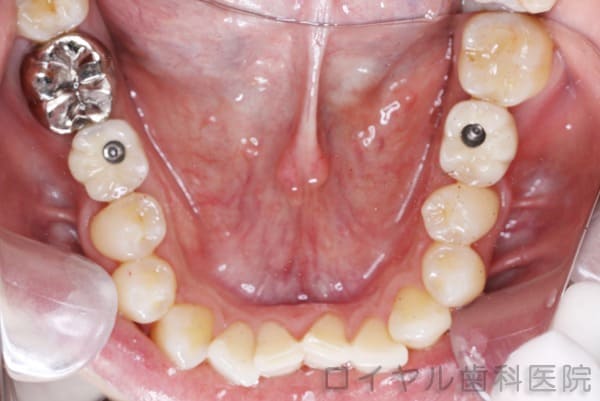

術後

-

装着直後です。

上の穴を白い樹脂で埋めて完了です。

- 治療内容

- 下顎右6番、左6番のインプラント治療

下顎右6番、左6番にインプラントを埋入したケースです。

【リスク・副作用】

お手入れが悪いと歯肉が腫れる場合があります。